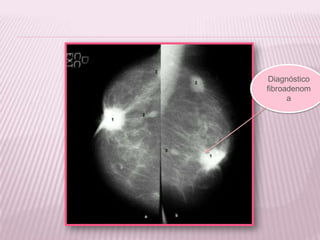

LESION BENIGNA:

FIBROADENOMA

Un fibroadenoma es un tumor benigno no

canceroso que se encuentra en

el tejido mamario.

Diagnóstico

fibroadenom

a